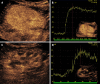

Kidney transplantation (KT) is an effective treatment for end-stage renal disease. Despite their rate has reduced over time, post-transplant complications still represent a major clinical problem because of the associated risk of graft failure and loss. Thus, post-KT complications should be diagnosed and treated promptly. Imaging plays a pivotal role in this setting. Grayscale ultrasound (US) with color Doppler analysis is the first-line imaging modality for assessing complications, although many findings lack specificity. When performed by experienced operators, contrast-enhanced US (CEUS) has been advocated as a safe and fast tool to improve the accuracy of US. Also, when performing CEUS there is potentially no need for further imaging, such as contrast-enhanced computed tomography or magnetic resonance imaging, which are often contraindicated in recipients with impaired renal function. This technique is also portable to patients' bedside, thus having the potential of maximizing the cost-effectiveness of the whole diagnostic process. Finally, the use of blood-pool contrast agents allows translating information on graft microvasculature into time-intensity curves, and in turn quantitative perfusion indexes. Quantitative analysis is under evaluation as a tool to diagnose rejection or other causes of graft dysfunction. In this paper, we review and illustrate the indications to CEUS in the post-KT setting, as well as the main CEUS findings that can help establishing the diagnosis and planning the most adequate treatment.